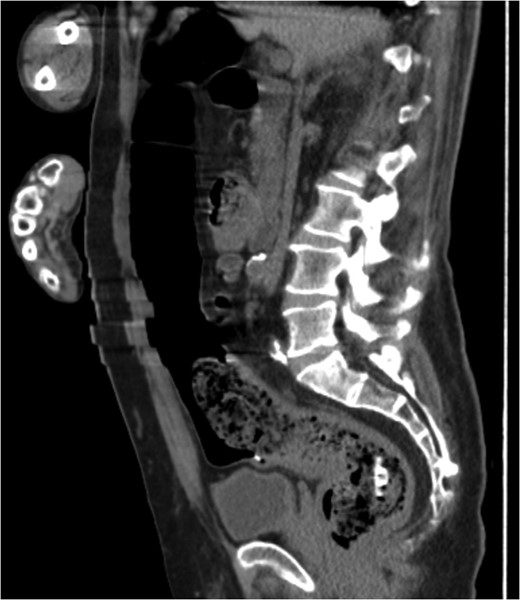

A 68-year-old male nursing home resident presented following dislodgement of a percutaneous endoscopic colostomy (PEC) tube originally sited to prevent recurrent sigmoid volvulus. Computed tomography demonstrated tube migration into the lumen of the recto-sigmoid junction, where it remained for 12 days before passing spontaneously. During this period, the patient remained asymptomatic; the residual colocutaneous fistula functioned as a decompressive valve. Originally, the patient was due to be discharged with early flexible sigmoidoscopy follow-up. However, complex social issues delayed discharge. During his admission, a second PEC tube was successfully inserted next to the previous colostomy site without complication. This is an unusual case and no similar episodes of asymptomatic PEC migration have been reported. We demonstrate that such cases may be offered an appropriate trial of conservative management. Here, we describe our experience and critically appraise the literature.

The patient remained asymptomatic with a soft, non-tender abdomen. The only abnormal clinical finding was the absence of a PEC tube from a patent periumbilical colostomy site.

The patient remained well and the PEC tube passed spontaneously on Day 12, during a bowel motion.

Tube migration leading to perforation and frank peritonitis has been described elsewhere [10]. However, there are no cases of asymptomatic dislodged PEC tubes. Following discussion with gastroenterology and colorectal surgery, the decision was made to let the PEC pass spontaneously or remove it during early follow-up flexible sigmoidoscopy. The PEC tube was naturally expelled on Day 12 without complication.